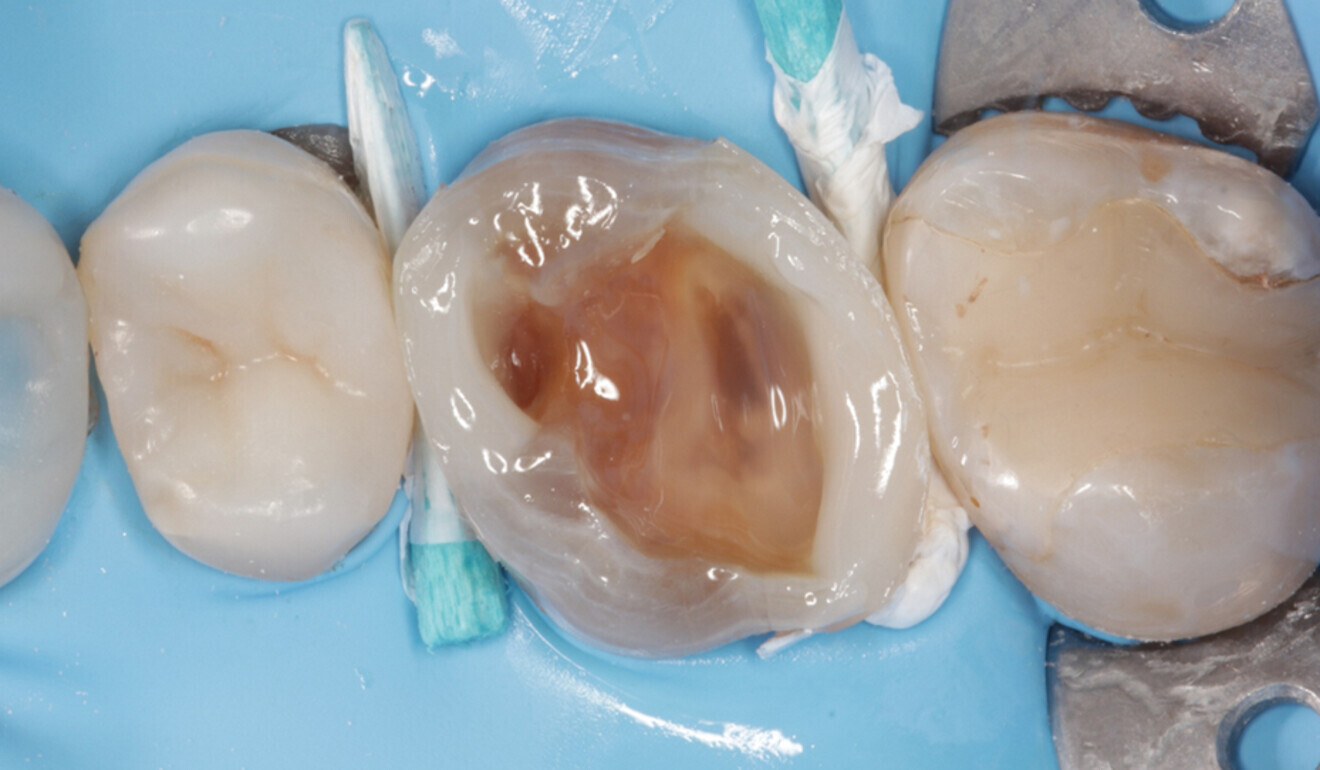

Fig. 6: Dental dam newly placed in the interproximal area. Full isolation is essential for the excavation of the infected dentine in the deepest part of the cavity. (Image: Kuraray Noritake Dental)

In accordance with the European Society of Endodontology’s guidelines on the management of deep caries,10 the deepest part of the cavity was cleaned under full dental dam isolation (Nic Tone, MDC Dental; Fig. 6). Carious tissue excavation was carried out using round burs and then the enamel and dentine were air abraded with 50 μm aluminium oxide (MicroEtcher IIA, Danville Materials). Multiple cracks, penetrating through the enamel and partially the dentine, had occurred within the mesial and palatal walls. The presence of cracks crossing the amelodentinal junction is an absolute indication for cuspal coverage.8, 11